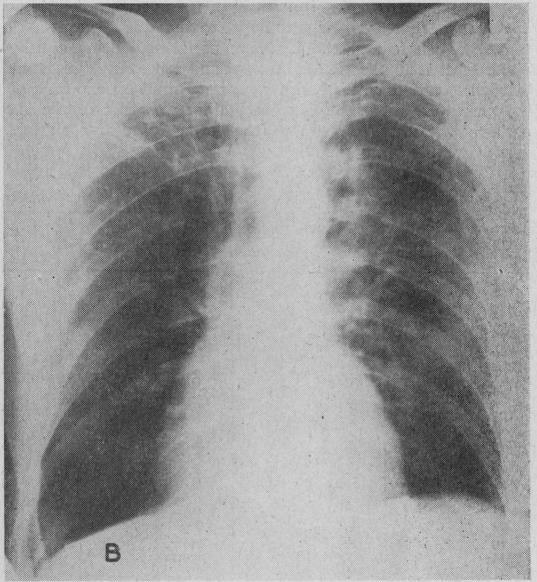

Surgical treatment of emphysema.

Br Med J. 1966 May 7;1(5496):1133-8. doi: 10.1136/bmj.1.5496.1133.